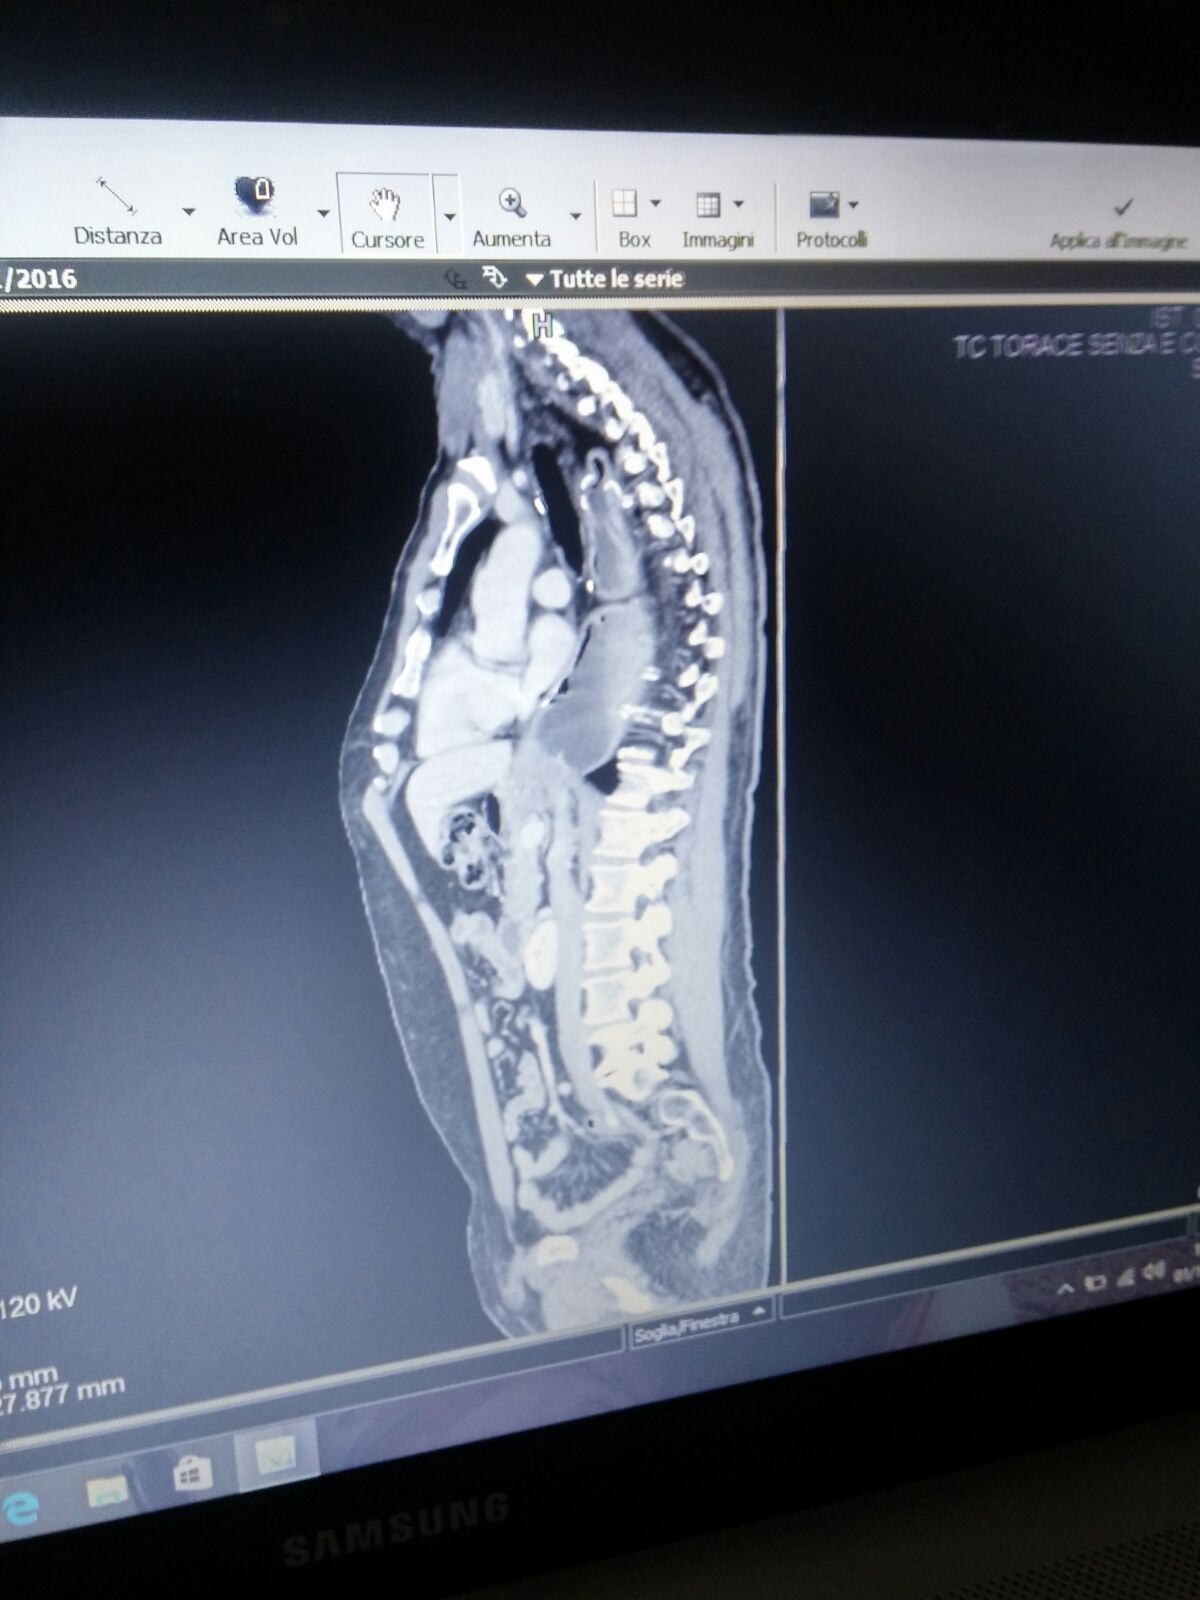

Commento file: Dicembre 2016

IMG-20161206-WA0009.jpg

[ 185.18 KiB | Osservato 1028 volte ]